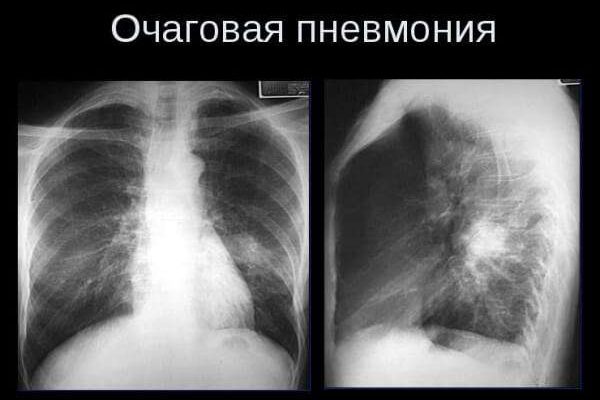

Очаговая пневмония (также известная как бронхиальная или бронхолегочная) — наиболее распространенная форма пневмонии, при которой инфекция распространяется на легочную ткань из бронхов и поражает небольшие участки легочной ткани — дольки легкого, которые включают альвеолы ​​и прилегающие к ним мелкие бронхиолы. калибра. Этот вид пневмонии может развиваться самостоятельно или быть вторичным, осложняя другие респираторные заболевания. Очаги воспаления могут располагаться как в легких, так и в разных областях, но чаще всего в их нижних долях.

В зависимости от количества и размеров воспаленных участков в паренхиме легких различают крупноочаговые и мелкоочаговые пневмонии, очаги могут быть одиночными и множественными. Выраженность и продолжительность клинических симптомов зависят от размера и количества воспалительных очагов.

На снимках одиночные очаги воспаления чередуются с участками с эмфиземой, микрометастазами. Это самый тяжелый вид курсов. Клиническая симптоматика больше похожа на круповую пневмонию. Необходимо интенсивное лечение, желательно в больнице.